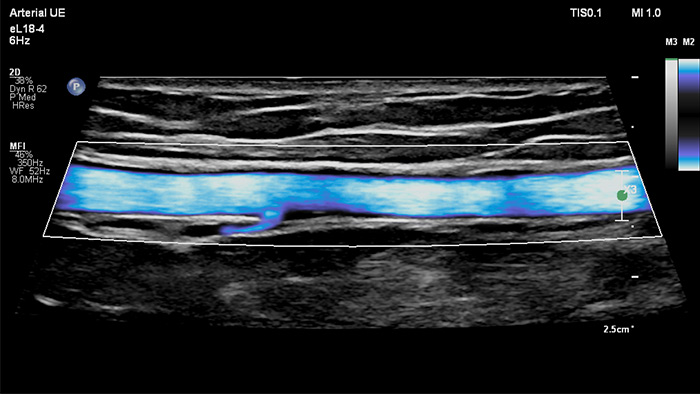

O MicroFlow Imaging da Philips foi concebido para detetar fluxo sanguíneo lento e fraco nas estruturas anatómicas do tecido com uma sensibilidade notável e melhorar a resolução do fluxo em exames vasculares. Com alta resolução e artefactos mínimos, os médicos podem visualizar e caracterizar perturbações subtis do fluxo à volta da placa estenótica para fazer diagnósticos confiantes.

The eL18-4 transducer is an ultra high-frequency linear transducer that incorporates ultra-broadband PureWave crystal technology with fine-elevation focusing capability, generating ultra-broadband frequencies from 2 to 22 MHz. The transducer’s advanced design allows for wide field-of-view trapezoid imaging and superb 2D detail resolution. It supports a broad range of high resolution applications including breast, small parts, vascular, pediatric and musculoskeletal imaging along with the penetration needed in obstetrical and gynecological examinations to help elevate clinical confidence.